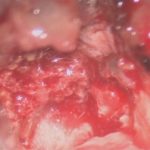

711

'25年12月

60代

良性頭蓋咽頭腫

頭蓋内腫瘍摘出術

No.’25_113 摘出 前

No.’25_113  摘出 中

No.’25_113 摘出 後